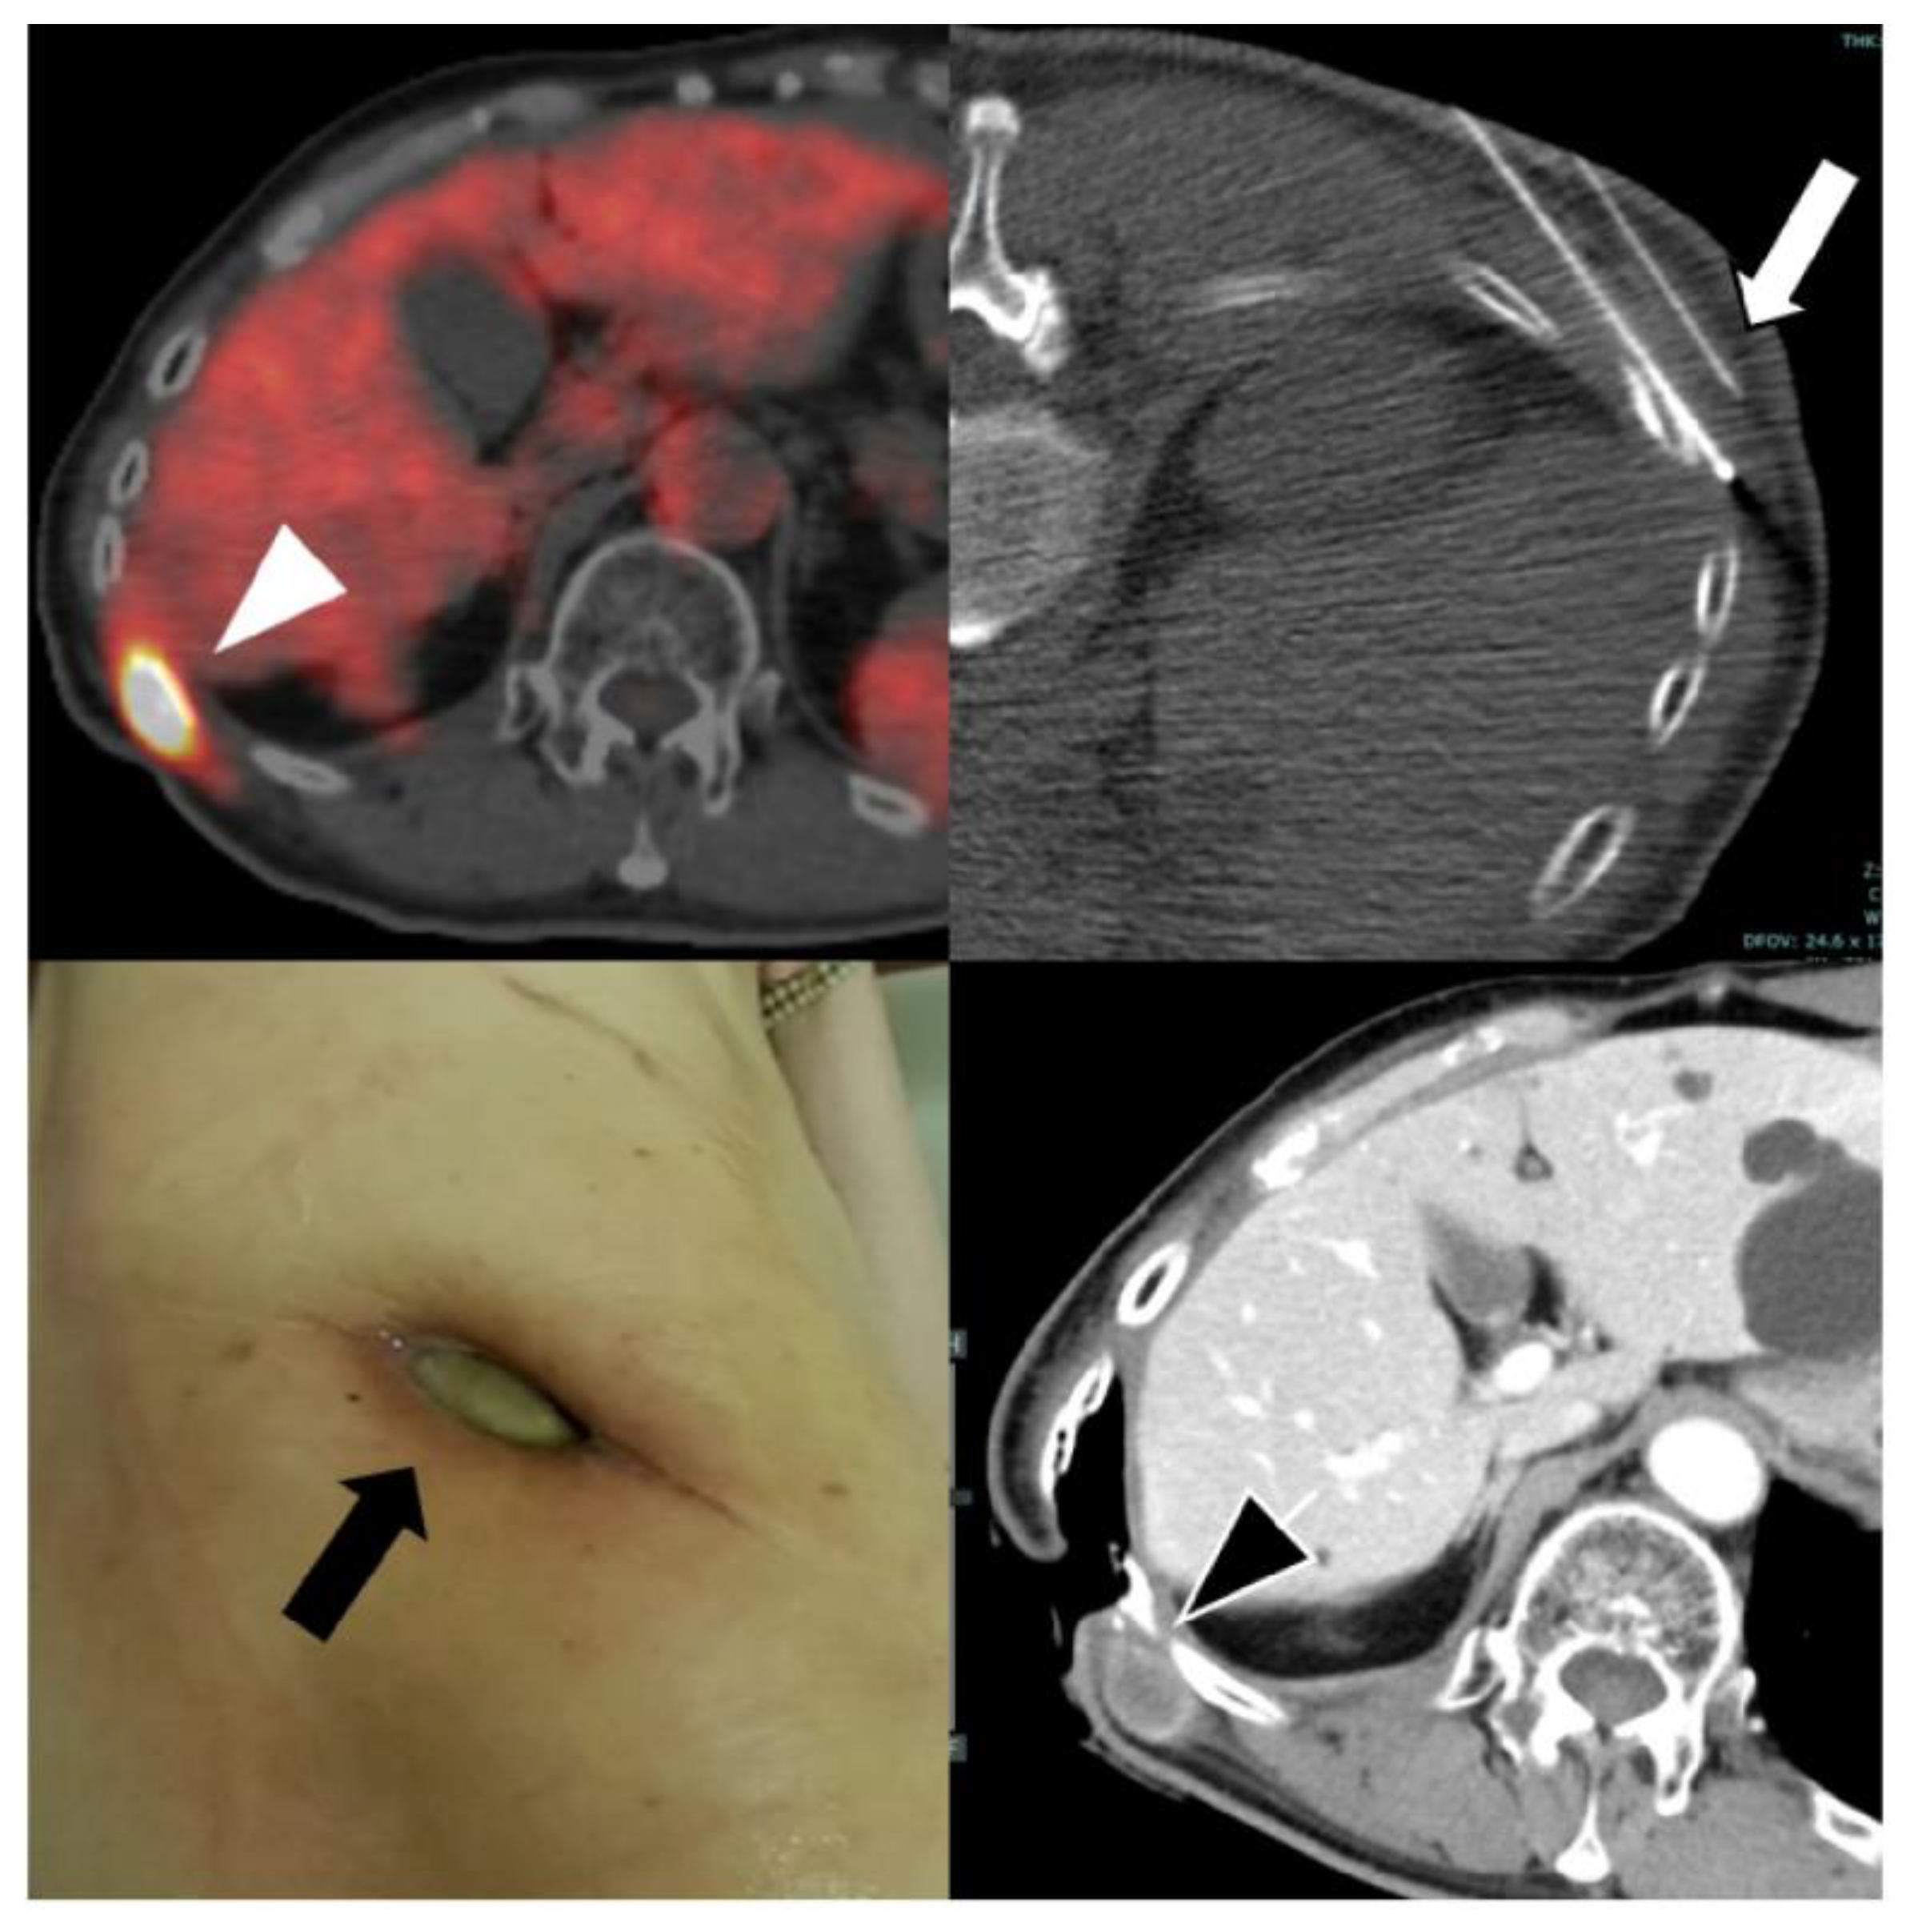

Background/Objectives: Pleural mesothelioma (PM) frequently recurs despite multimodal therapy. Here, we aimed to retrospectively evaluate the safety and potential clinical benefit of radiofrequency ablation (RFA) for recurrent PM. Methods: Fourteen consecutive patients underwent CT-guided RFA between July 2019 and June 2025. The cohort comprised 13 men and 1 woman, with a median age of 69 (range, 54–77) years. All patients had previously received systemic therapy and 12 had undergone surgery. Seven patients (50%) presented with multiple lesions, and 25 tumors (median diameter 1.8 cm; range, 0.5–7.0 cm) were treated in 23 sessions. Outcomes assessed were local tumor control, complications, and survival. Local progression and overall survival were estimated using Kaplan–Meier analysis. Adverse events were classified according to the Society of Interventional Radiology guidelines. Results: Technical success was achieved in all sessions. Two tumors showed local recurrence, corresponding to 1- and 2-year local progression rates of 10.6%. Seven patients showed distant metastases, most of whom subsequently received systemic therapy. Three patients died, two from disease progression and one from treatment-related gastrointestinal perforation during therapy for an unrelated cancer. The overall survival rates were 100%, 100%, and 60% at 1, 3, and 5 years, respectively. Major and minor complications occurred in one case each (4.3%): a refractory skin ulcer and retroperitoneal hematoma, respectively. Conclusions: RFA was technically feasible and generally well tolerated, and helped achieve encouraging local control and survival in patients with recurrent PM, warranting further evaluation of RFA as a complementary approach in multimodal treatment strategies.